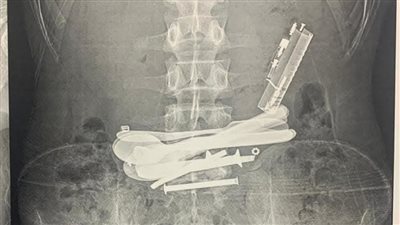

ولاعات ومقصات وسبح.. إنقاذ مريض ابتلع أجسامًا معدنية بمستشفى سوهاج الجامعي